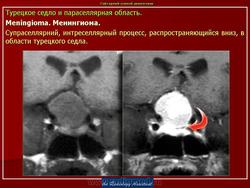

Менингиома составляет И-31 % всех внутричерепных опухолей, причем в 3-5 % случаев она локализуется под нижней поверхностью мозга, от переднего края орбиты до большого затылочного отверстия. Общепринято деление менингиом на три типа. Конвекситалышй тип располагается на выпуклой поверхности больших полушарий, парасагиттальный тип залегает в продольной щели мозга и связан с верхним продольным синусом и серповидным отростком. Базальный тип относится к обонятельной ямке и малому крылу клиновидной кости. Он может обладать различной локализацией: супра- и параселлярной, тенториальной, мостомозжечковой и др. По биологической активности менингиомы бывают трех типов.